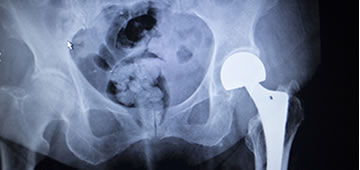

La artroplastia de cadera es el procedimiento quirúrgico mediante el cual se reemplaza la articulación de la cadera por un elemento artificial, conocido más comúnmente como prótesis, que suele estar compuesto de titanio u otras aleaciones metálicas. Existen muchos tipos de artroplastias de cadera, si bien la artroplastia total cementada suele ser la mejor opción a la hora de realizar esta intervención quirúrgica.1 La elección a la hora de colocar un tipo de prótesis u otra responde al tipo de lesión que ha propiciado la cirugía, así como la edad y características del paciente y los propios criterios del cirujano.

Este tipo de intervención es una de las más comunes dentro de la cirugía traumatológica, y se estima que en todo el mundo se realizan unas 300.000 cirugías de artroplastia de cadera al año.1,2 Debido a esto, y pese a ser una cirugía de gran complejidad, la gran mayoría de estas intervenciones salen adelante sin contratiempos, siendo el índice de mortalidad uno de los más bajos en toda la cirugía traumatológica (23 muertes cada 40.000 cirugías, un 0,0006 %), y normalmente estos casos suelen deberse a otras complicaciones o patologías asociadas que el paciente pudiera presentar, como trastornos de coagulación, infecciones, patologías malignas.